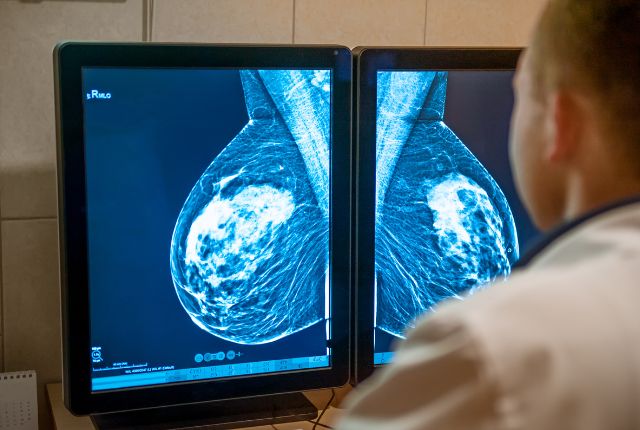

Radiographie : permet une première visualisation des structures internes du corps et peut aider à détecter certaines anomalies. Par exemple, la mammographie est couramment utilisée dans le dépistage du cancer du sein.

Échographie : utilise les ultrasons pour examiner les tissus et préciser la nature d'une lésion, notamment dans le cadre des cancers mammaires.